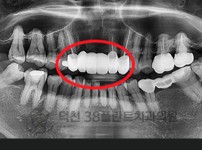

치료전후